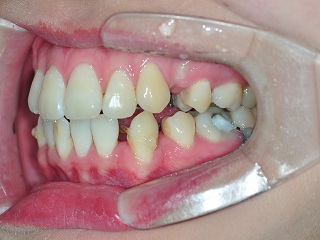

이번 월치료를 가기 전에 견과류를 씹어먹다가 상악 가장 끝자리의 어금니에 연결되어있던

와이어가 브라켓 교정장치에서 튀어나왔어요ㅠ,ㅠ 조심히 먹는다고 씹었는데… ㅠㅠ

이번 월치료에는 상악 어금니에 탈락되었던 브라켓을 부착하고 상악에 와이어 교체, 고무줄 교체가 이루어졌어요.

상악 스크류에 연결된 고무줄을 제거하였고, 하악 송곳니에 고무줄교체,

앞니부분에 고무줄연결을 해주셨어요.

상악 송곳니에 부착되어있던 가치(가짜치아)를 제거했습니다.